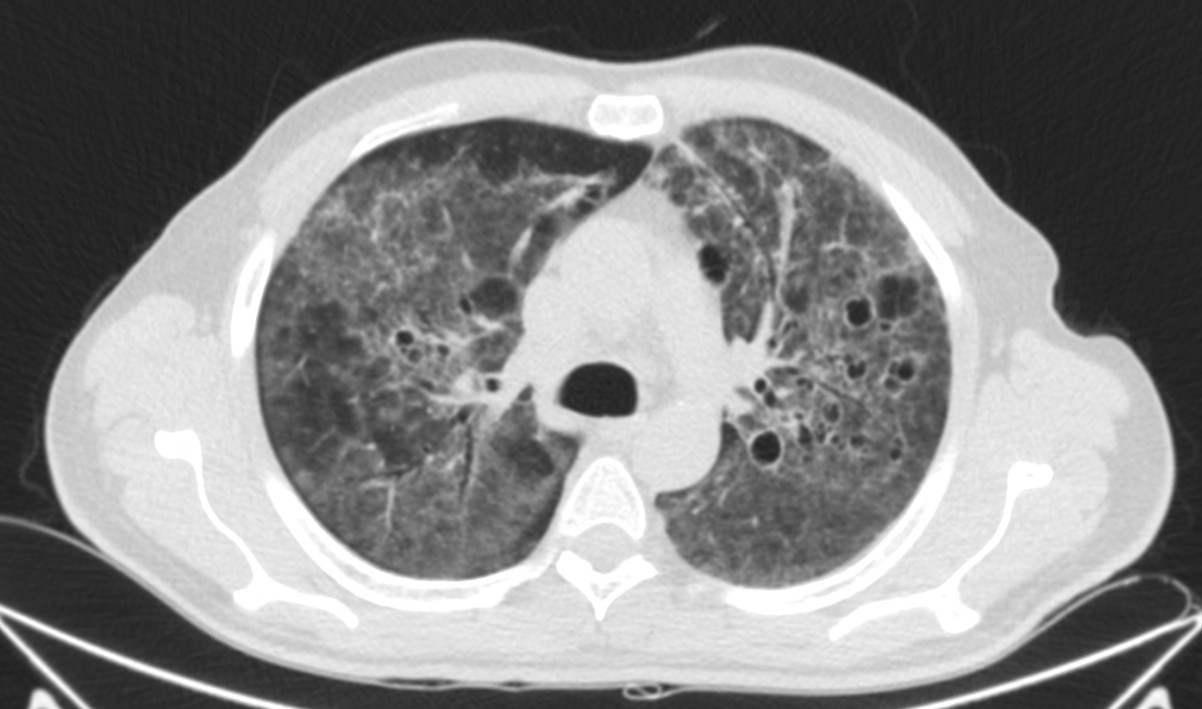

Describamos los hallazgos:

TAC: Vidrio deslustrado difuso y perihiliar frecuente, infiiltrado reticular, consolidaxión y patrón de árbol en brote, engrosamiento de septos, patrón en empedrado, derrame pleural, quistes.